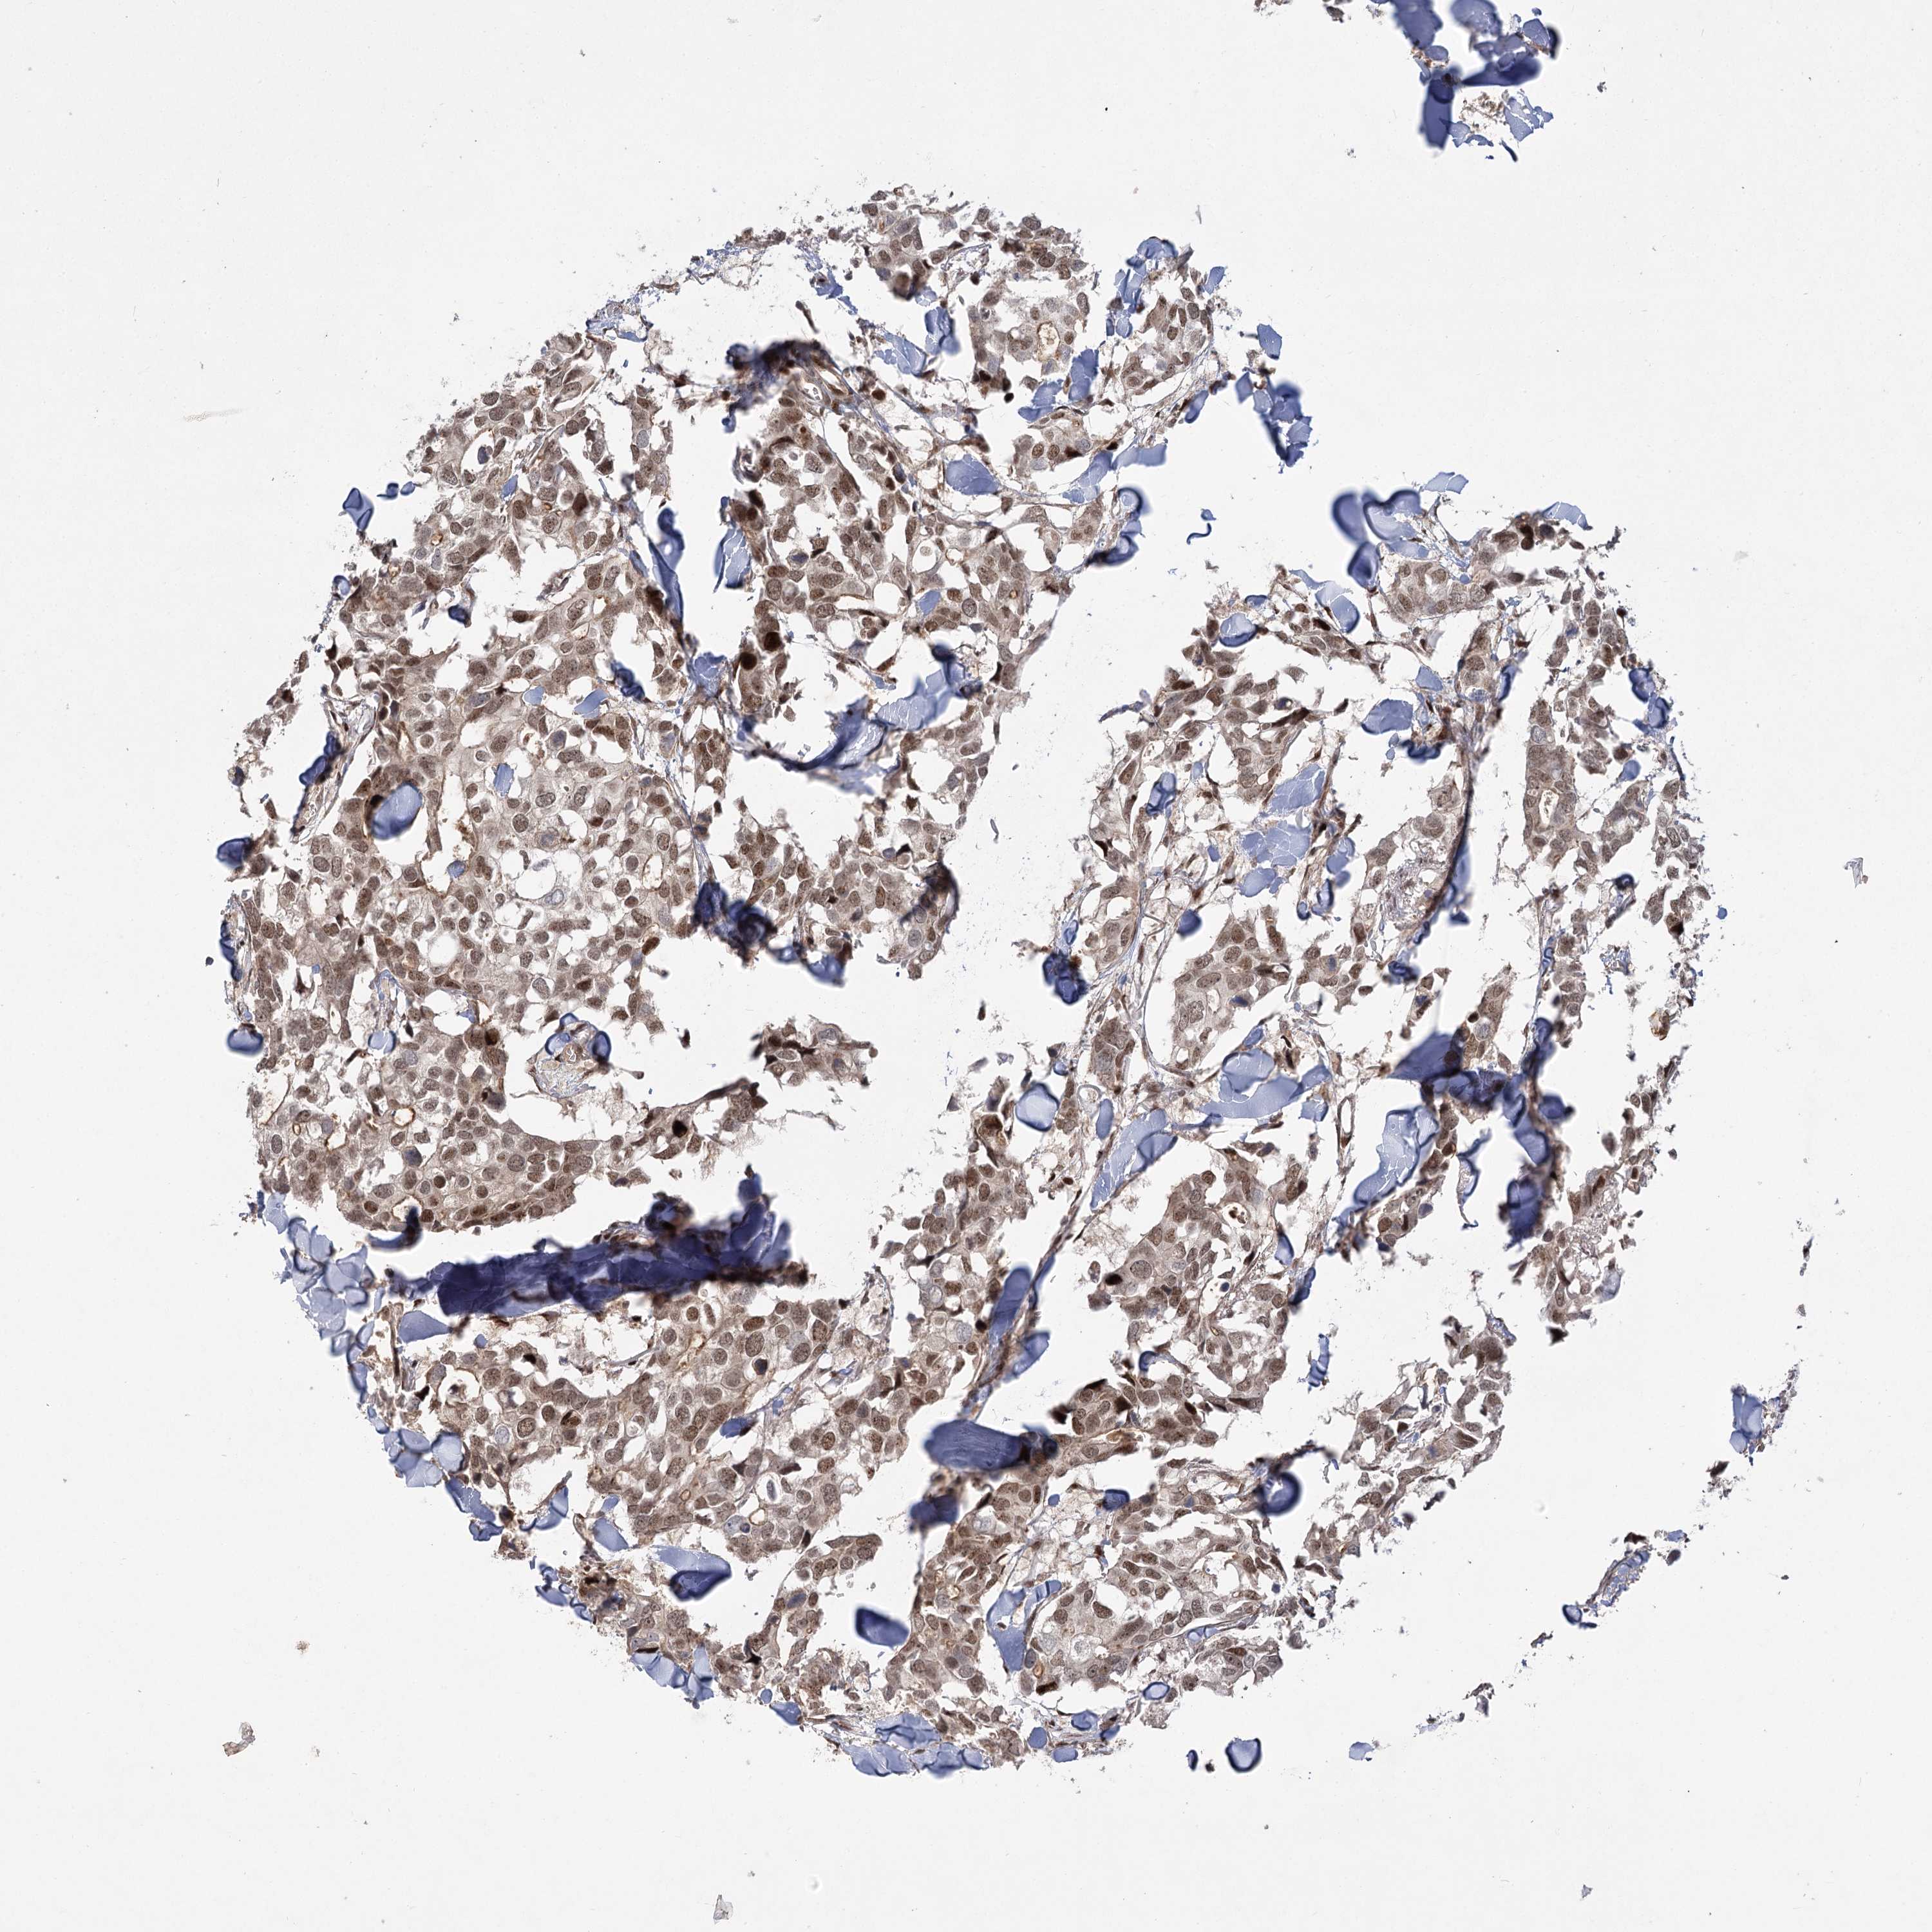

BRCA TCGA BRCA VALIDATION PROTEIN EXPRESSION

Breast cancer

Human cancer